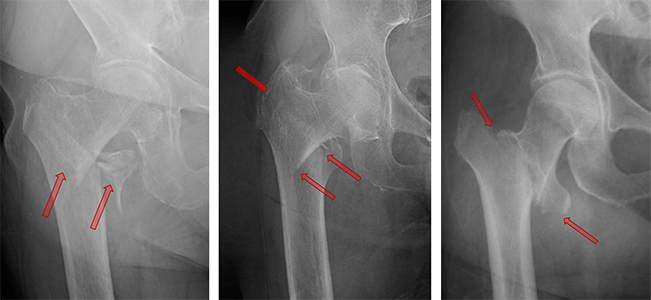

• Всестороннее знание плюсов и минусов лечения переломов шейки бедренной кости фиксацией полыми винтами

Всестороннее знание плюсов и минусов лечения переломов шейки бедренной кости фиксацией полыми винтами

2022-12-05

Перелом шейки бедренной кости является одной из наиболее часто встречающихся в клинической практике ортопедических травм, при этом у большинства пожилых пациентов на долю переломов бедра приходится более 50%.Согласно статистике, частота переломов шейки бедра в последние годы постепенно увеличивается, при этом

• 5 самых горячих проблем перелома шейки бедра, с которыми сталкиваются ваши коллеги!

5 самых горячих проблем перелома шейки бедра, с которыми сталкиваются ваши коллеги!

2022-09-28

Выбор внутренней фиксации по сравнению с заменой сустава В настоящее время считается, что внутренняя фиксация полым стержнем при переломе шейки бедра имеет преимущества короткого времени операции, небольшой травмы и низкой стоимости, но у большинства пожилых пациентов наблюдается остеопороз, поэтому стабильность